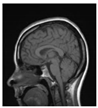

The signing process introduces the stages of signing and encrypting the data as shown in Figure 2. The medical image is applied as a plain image, and the cipher image will be a signed image by using the block content-based technique. The marked image is then encrypted to increase the level of security. The proposed technique is applied on the DWT sub-bands of the image. The signing process is described below:

Figure 2.

Signing process.

Stage 1: Compute the 2D-DWT of the original medical image A. This operation generates four quarters LL, HL, LH, and HH. Each sub-band is a matrix of DWT coefficients at a specific resolution. Then, the four sub-bands are divided into (8 × 8) blocks.

Stage 2: For each sub-band, permutation is done by replacing coefficients from right to left, bottom to top through DCT coefficients of (LL, HL, LH, and HH) sub-bands.

Stage 3: For the first row and first column of each DCT, the coefficients for each block in the first sub-band (LL) are substituted by the last row and last column, respectively, of a corresponding block in the second sub-band (HL). For first row and column of each DCT, coefficients of each block in the third sub-band (LH) are substituted by the last row and column of a corresponding block in the fourth sub-band (HH). Then, IDCT and 2D-IDWT are applied.

Stage 4: The signed image is encrypted using DRPE encryption technique.

Table 1 shows the original image, marked image, encrypted image, the decrypted image, and the correlation between extracted blocks and original blocks after decryption using the Double Random Phase Encryption. It is clear that the encryption increases the security, and the mean correlation between the recovered mark and the original mark is measured to be 0.9 in both cases.

The PSNR and SSIM between the original image and marked image are 35.99 db and 0.97, respectively, which means that the marking does not affect the quality of the original image and keeps the invisibility of mark in the image. After encrypting the marked image using the DPRE algorithm, the results show that PSNR and SSIM between the encrypted and marked image are 12 db and 0.1, which verifies the strength of the suggested cryptosystem, as there is no similarity between them. Moreover, the results show that the correlation between the embedded rows and columns with the original is near to 1, verifying the robustness of the mark or signature.